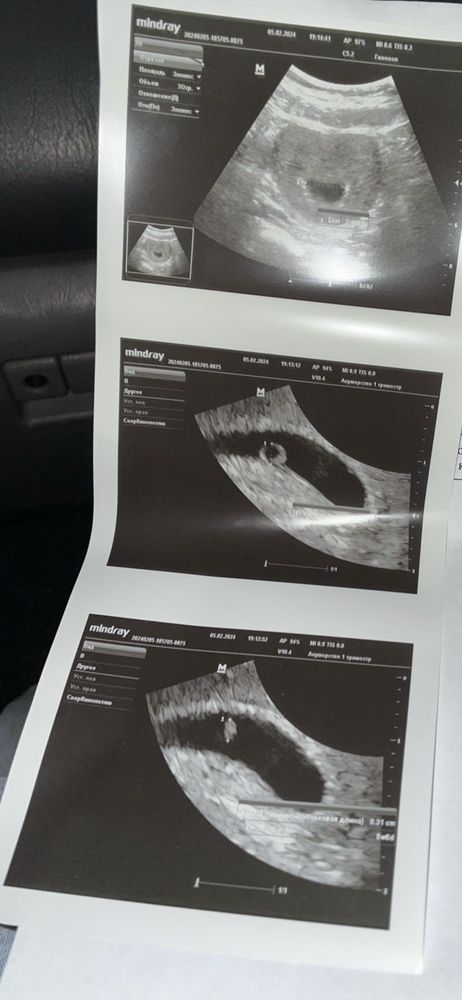

У меня сначала точка была

А почти через пару недель малюсенький эмбриончик и желточный мешочек